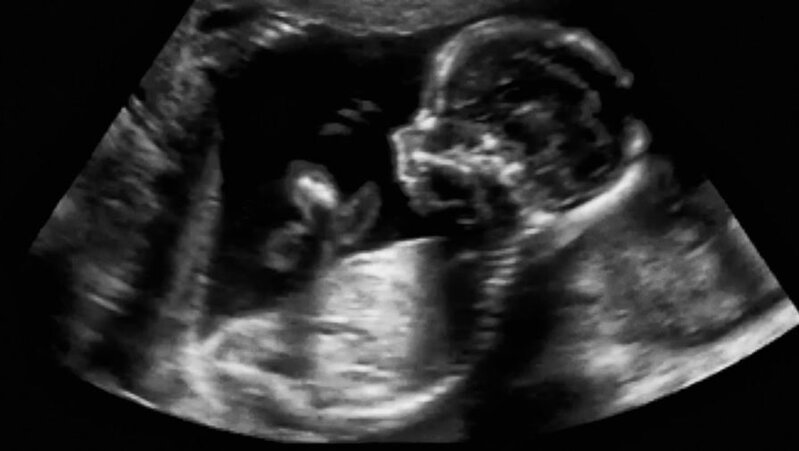

Morozova adlı qız qarın ağrısı şikayəti ilə həkimə müraciət edib. Müayinədən sonra həkimlər məktəbli qızın hamilə olduğunu müəyyən ediblər.

Həmçinin hamiləliyin riskli olduğunu bildiriblər.

O, xəstəxanaya yerləşdirilib, vəziyyəti orta-ağırdır.